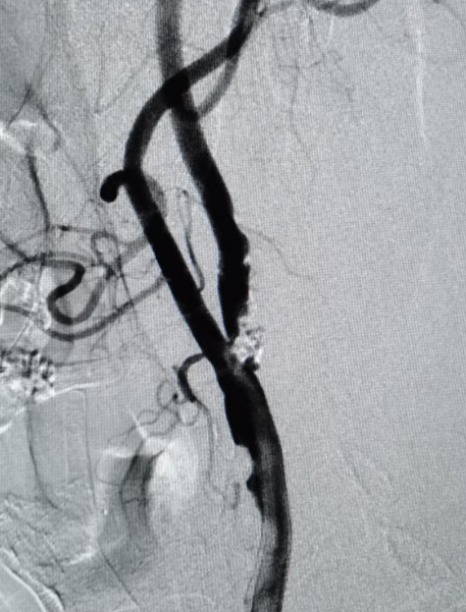

中年男性。因长期头晕,多处求诊均不能明确原因后,来到海南西部中心医院神经内科就诊。经脑血管造影发现患者椎动脉闭塞,右侧椎动脉重度狭窄,小脑、脑干长期缺血。

术前DSA

考虑到患者病情复杂、预期手术难度高、风险大,神经内科介入团队根据实际情况,为患者置入了全国首款maurora雷帕霉素药物洗脱支架。术后造影显示,其右侧椎动脉狭窄解除,脑供血不足明显改善,患者恢复良好。据悉,此次椎动脉药物洗脱支架置入术属我院首次开展,成功填补了海南西部地区脑血管介入治疗的空白。

术后DSA